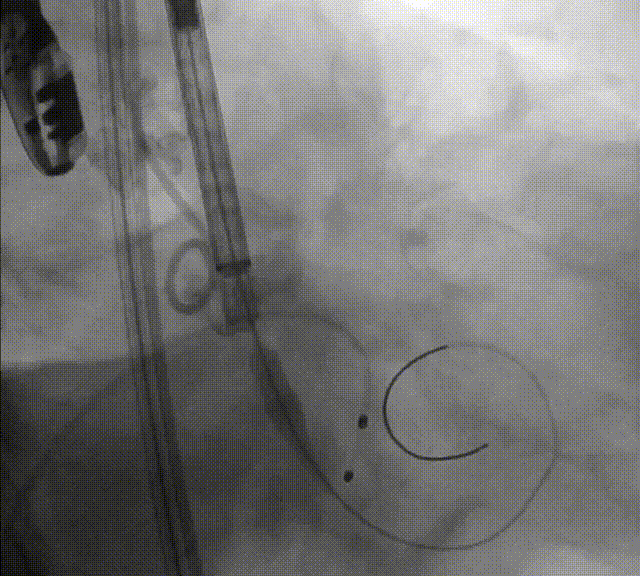

后扩否?

瓣膜是否有弹出风险?如何避免?

再次与根部造影对比

通过与术前主动脉根部造影的对比,确认两侧深度平均但较临界,可谨慎操作下尝试球囊后扩张以使流入端瓣架充分膨胀贴合自体瓣环,减少瓣周漏。

23mm Z-Med后扩张

当瓣膜完全释放后,瓣架仍呈“收口”形态,应充分评估后扩风险与获益,决定是否要后扩;

如需后扩,球囊充盈时建议轻推球囊,且待完全回抽球囊后再停起搏 ,以降低瓣膜脱位风险。